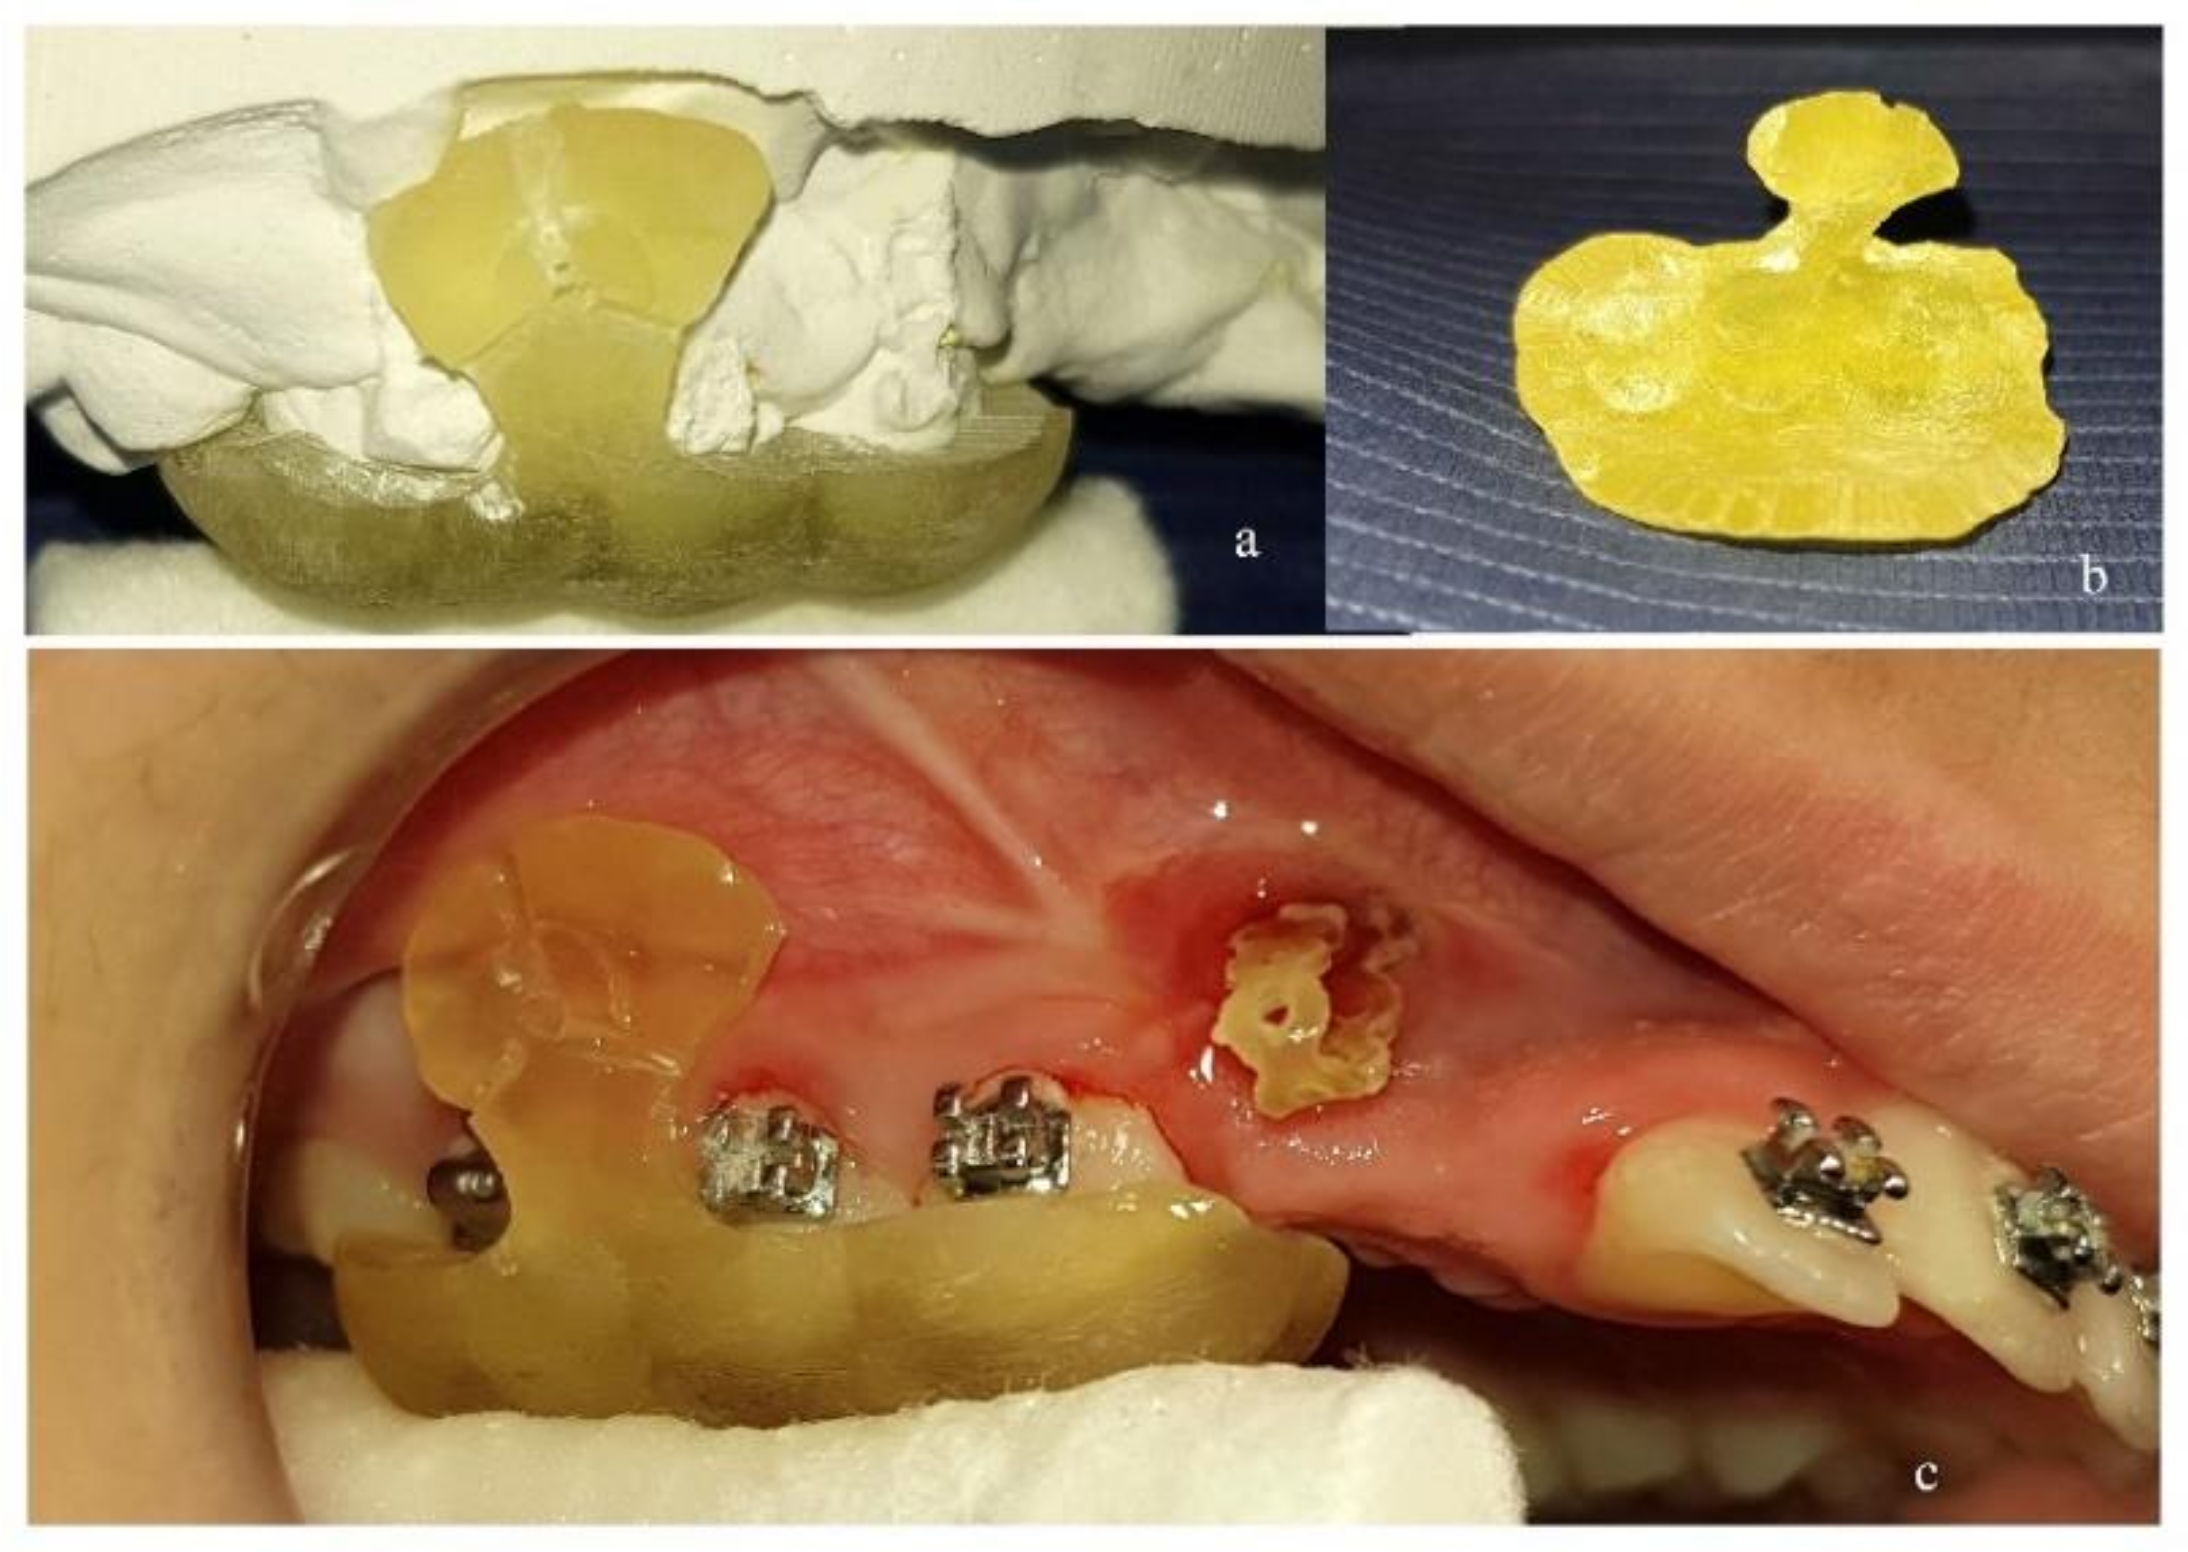

The design of the surgical guide was done by drawing a peripheral line on the digital model, mostly leaning on occlusal surfaces with a projection to the area of placement (Figure 1c). The thickness of the guide was set to 2 mm. Guiding holes for mini-implants were incorporated on the guide and the diameter was set exactly as the diameter of the real mini-implant (1.5 mm-1.4 mm-1.3 mm). The length of the guiding holes was designed to be 3 mm, providing satisfying guidance for placing the mini-implant (Figure 1d). The surgical guide was then exported as a .stl model (Figure 1e) and then 3D-printed in a biocompatible resin on a Formlabs Form 2 3D-printer.

The surgical guide was first tested for proper fitting on a plaster model of the patient’s dental arch (Figure 2a,b) and then on the teeth and mucosa in the patient’s mouth (Figure 2c). Care was taken so that the edges of the surgical guide would not interfere with molar tubes or brackets. For that purpose, proper grinding was performed. This is of great importance, as design of the surgical guide on the digital model imposes some compromises concerning contact of the guide with fixed appliances.

Figure 2. (a) Surgical guide 3D-printed in biocompatible resin and tested for proper fitting on plaster model. (b) Inner side of the surgical guide. (c) Surgical guide tested for proper fitting in patient’s mouth.